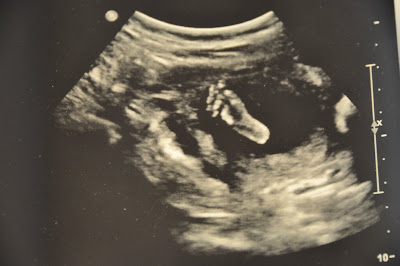

Here are some pictures from Friday.